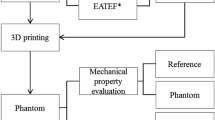

3D printing technology is particularly well suited to the fabrication of various kinds of patient-specific phantoms based on medical images. To develop a more realistic phantom, 3D printing, as well as silicone casting and coating are needed. Therefore, various steps were required to fabricate patient-specific phantoms using 3D printing technology and silicone moulding simultaneously in this study (Fig. 5). First, based on medical images such as CT and MR, the segmentation of various kinds of anatomic parts involving difficult tracheal intubation such as skin, mandible, cranio-maxilla, back of the skull, airway, cervical spine (c-spine), and tongue was performed. The model was designed to consider realistic movements of the jaw and c-spine, and similar mechanical properties of the tongue, airway, and skin. In addition, the airway part was designed to be replaceable. To fabricate each anatomy part, adequate 3D printing technology and materials were chosen by considering colour, size, weight, and texture7. A previous study demonstrated that Shore A hardness of newborns and children was estimated to be between 40 and 60 A9. The simulator was evaluated by measuring the distance of the mouth opening and the shape accuracies between STL and each 3D printed phantom. In addition, the Shore A hardness of the airway and tongue was measured to assess the similarities to those of a toddler. The overall procedure of manufacturing a difficult tracheal intubation simulator is illustrated in Fig. 5.